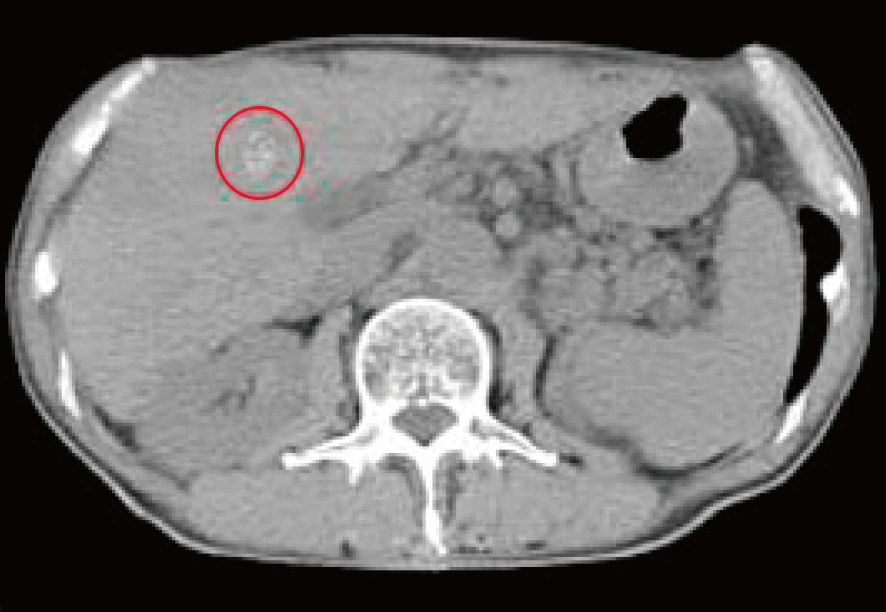

治療前CTでは肝臓右葉にラジオ波治療の痕跡と、その周囲(赤マルで囲んだ内部のやや濃い色調部分)に

再発・拡大したがん腫瘍を認めた。